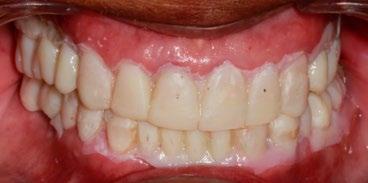

El tratamiento concluyó en 2 años y 6 meses, logrando el perfil facial deseado, con clase I esquelética, clase I canina y molar bilaterales, corrección del apiñamiento maxilar y mandibular, líneas medias coincidentes, overjet y overbite adecuados, así como la realización de la genioplastia e implantes en la zona malar. En los

estudios radiográficos finales, en la lateral de cráneo, se observa la diferencia tras 2 años de iniciado el tratamiento (Figura 8), además de la radiografía panorámica final. Debido a la forma del perfil, y con el fin de alcanzar la estética deseada, se realizó la cirugía.

En los estudios finales en las fotografías intraorales (Figura 9) se ve la línea media coincidente, el overjet y el overbite. La alineación y forma de las arcadas superior e inferior, con el

Figura 9. Lateral derecha frente, izquierda final.

retenedor fijo de premolar a premolar (Figura 10).